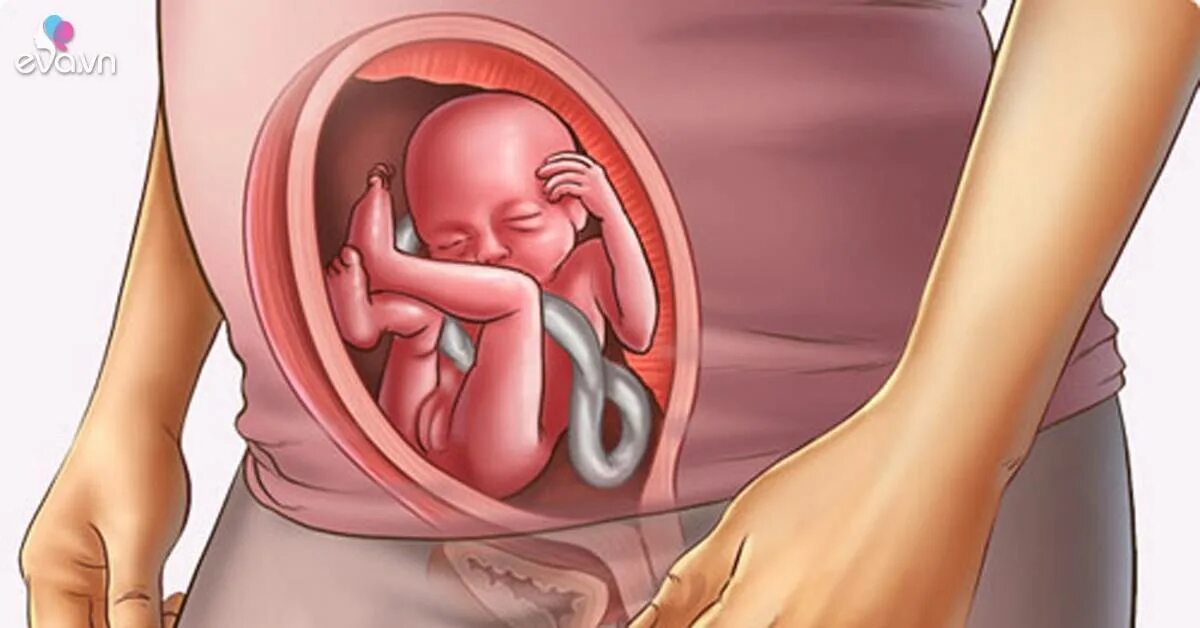

20 недель часто шевелится